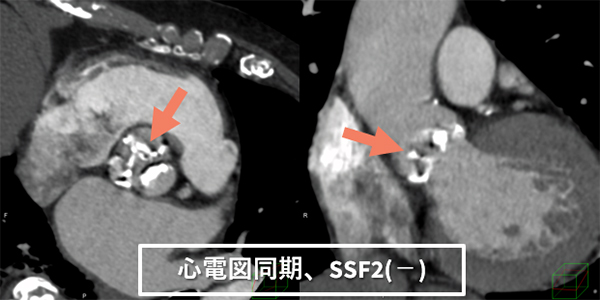

図5 TAVI 術前計測CT

装置更新前はTAVI術前の大動脈弁計測において、モーションアーチファクトのある状態で計測することが多かった。Revolution CTにおいても、管球回転速度は上昇したが、弁が最大拡張した位相でモーションアーチファクト(→)を抑えた画像を取得することは困難であった。

しかし、SSF2を使用することにより、弁のモーションアーチファクトが抑えられ(→)、計測をより簡便に、精度よく行えるようになった。